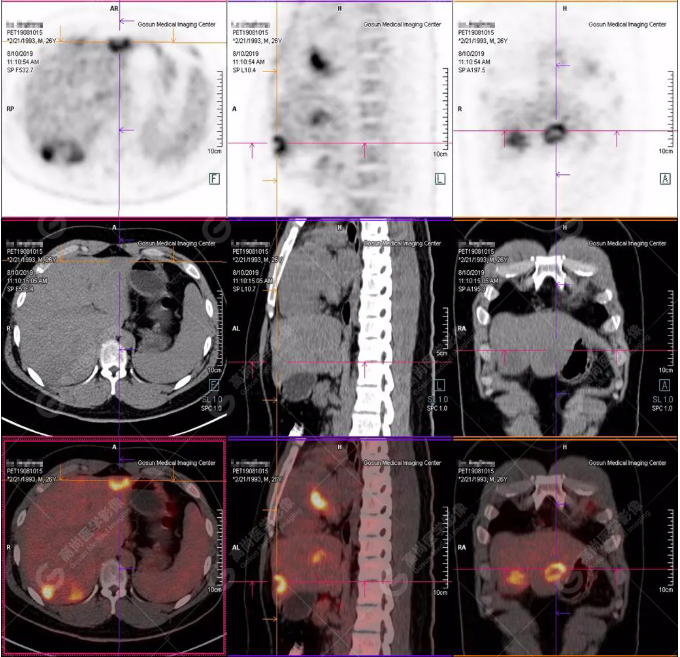

B超及CT檢查發(fā)現(xiàn):肝臟多發(fā)低密度占位。

PET/CT全身圖

PET/CT診斷

嗜酸性粒細(xì)胞增多癥肝浸潤